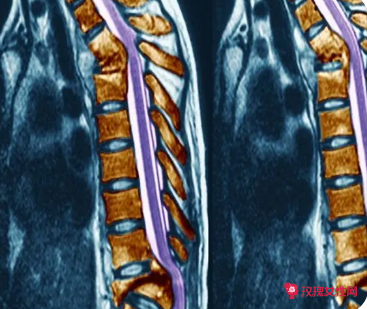

image.png